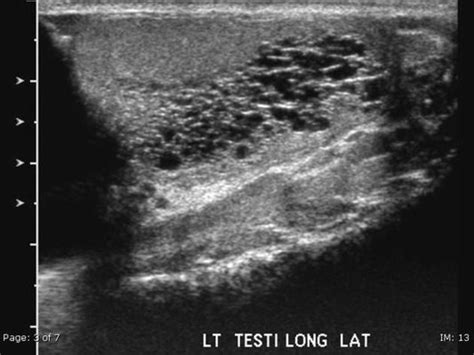

Ultrasound print of a transverse scan of normal testis ...

Ultrasound print of a transverse scan of normal testis ... from www.researchgate.net